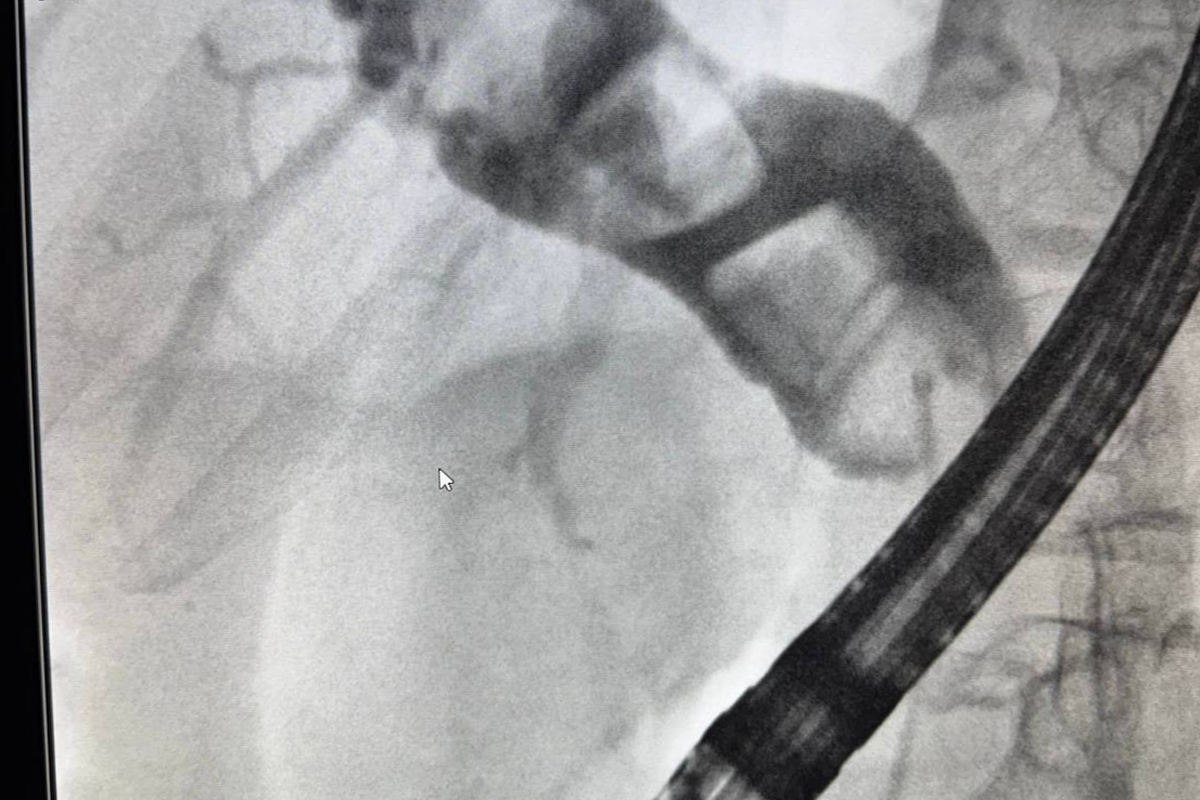

Мужчина был экстренно доставлен в тяжелом состоянии и болями. Обследование выявило, что камни перекрыли желчные протоки. Врачи успешно провели операцию по их удалению. Всего через 4 дня пациента выписали в удовлетворительном состоянии.